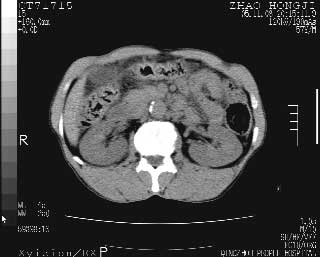

临床资料:男性,57岁,上腹部疼痛并5天,突然加重并延及全腹伴恶心5小时入院。胰淀粉酶化验在正常范围。检查:腹肌紧张,全腹压痛、反跳痛,尤以右上腹部为著。肠鸣音减低。血常规:wbc14.6x10/9, n:11.3x10/9 ,血压:135/90mmhg. 胸部透视:腹部肠腔轻度张气,未见其它异常改变。

肝右前缘少量积气,其他未见明显异常.考虑上消化道穿孔.

小网膜囊积气液,胃壁僵硬。考虑胃穿孔。

小膜网膜积液,肝缘气腹征,上消化道穿孔。

胰腺形态规则,胰周脂肪间隙清晰,结合临床可排除急性胰腺炎

从图提示我同意空腔脏器穿孔的诊断,来源肠道{由于病程较短,故没能见到肠系膜聚局的征象}。

肝缘见少许气体,胰尾部见少许气体包饶(蓝色圈),12指肠上部或球部邻近胆囊周边也可见少许气体影(黄色圈),并忖托出胆囊壁,12指肠远段肠道内未见明显气体(白色箭)。

肝脏前缘见少量积气、胰尾部见少许气体包饶,肾前筋膜未见增厚,临床淀粉酶不高,意见:上消化道穿孔。

消化道穿孔。12指肠球部周和胰周积气考虑12指肠穿孔可能性大。

入院3小时后行剖腹探查术,见腹腔内大量脓性混浊液约1000ml,十二指肠球部溃疡穿孔,溃疡面约2.5x2cm,穿孔直径约0.6cm。胃内容物外益,周围组织炎性水肿明显。行十二指肠穿孔修补术。术后诊断:

1、十二指肠溃疡穿孔

2、弥漫性腹膜炎

对于少量的腹腔游离气体,ct检查较普通透视有绝对的优势,它不仅可以看到肝脏前上缘的气体,而且还能够看到小网膜区的游离气体。从而可以肯定诊断。各位分析战友的很好,感谢大家的参入!